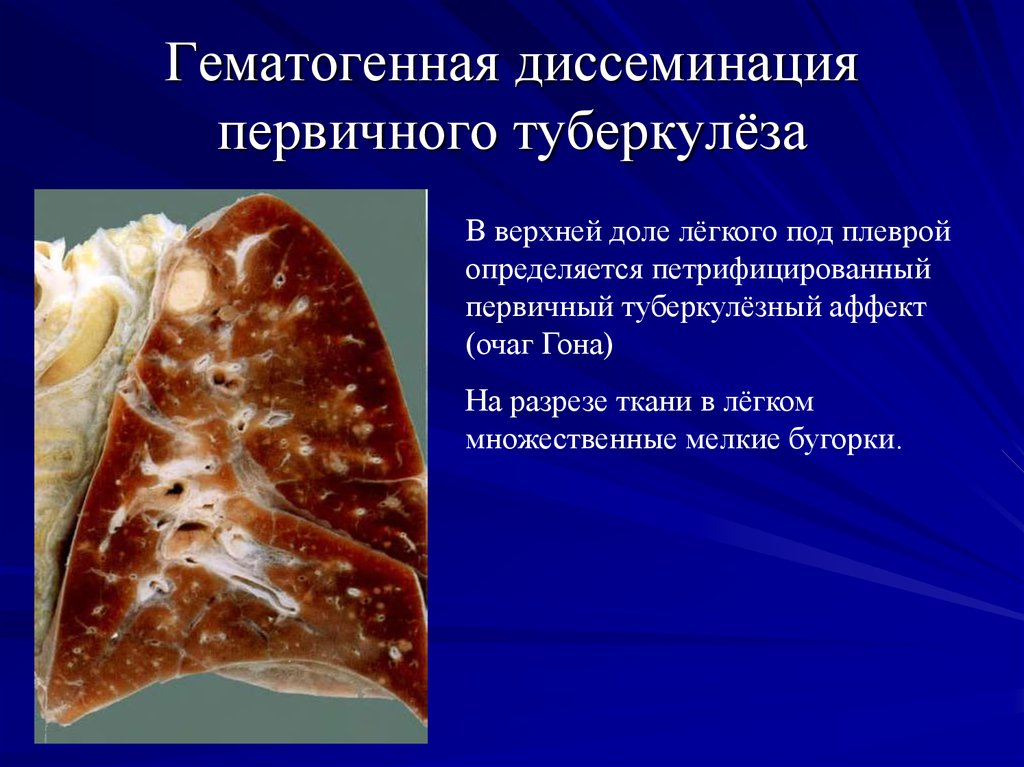

В клинической картине острого гематогенно диссеминированного туберкулеза преобладает